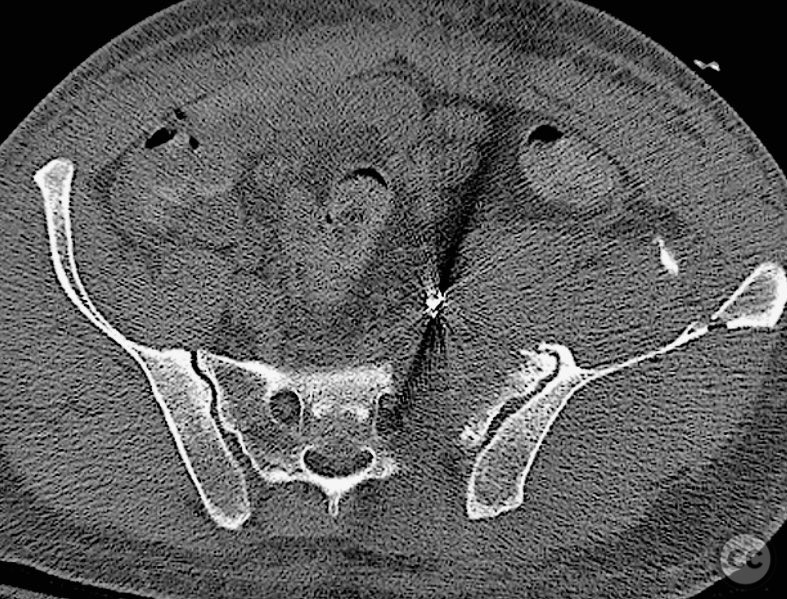

Clinical and radiological findings:  A 42-year-old male sustained a high-energy motor vehicle accident resulting in an unstable pelvic ring injury (AO/OTA 61-C1.3) with hemodynamic instability and associated intraperitoneal bladder rupture. Initial computed tomography demonstrated a complex anterior pelvic ring disruption and a posterior sacral fracture with contrast extravasation and blood within the fracture site. The patient was hemodynamically unstable on presentation.

Anatomical surgical approach:  The anterior approach utilized a Pfannenstiel incision to access the symphysis pubis and pubic rami, with subperiosteal dissection of the rectus abdominis and exposure of the retropubic space for reduction and fixation. For posterior sacral ORIF, a midline longitudinal incision was made over the sacrum, with subperiosteal elevation of the paraspinal musculature to expose the sacral fracture. A tenaculum clamp was applied for direct reduction, followed by percutaneous insertion of iliosacral screws under fluoroscopic guidance.

The case was notable for initial successful multidisciplinary management of both hemodynamic instability and intraperitoneal bladder injury, allowing for staged surgical intervention. Despite accurate anterior pelvic reduction and fixation, postoperative imaging revealed worsening posterior sacral displacement, necessitating subsequent posterior open reduction. The use of a tenaculum clamp facilitated direct anatomical reduction of the sacral fracture prior to iliosacral screw fixation. The presence of an embolic coil from prior angioembolization did not impede surgical access or hardware placement. This case demonstrates that initial anterior pelvic ORIF does not complicate or preclude subsequent routine posterior pelvic ORIF in complex unstable ring injuries.

Orthopaedic implants used:   Anterior pelvic reconstruction plate, iliosacral cannulated screws, tenaculum reduction clamp